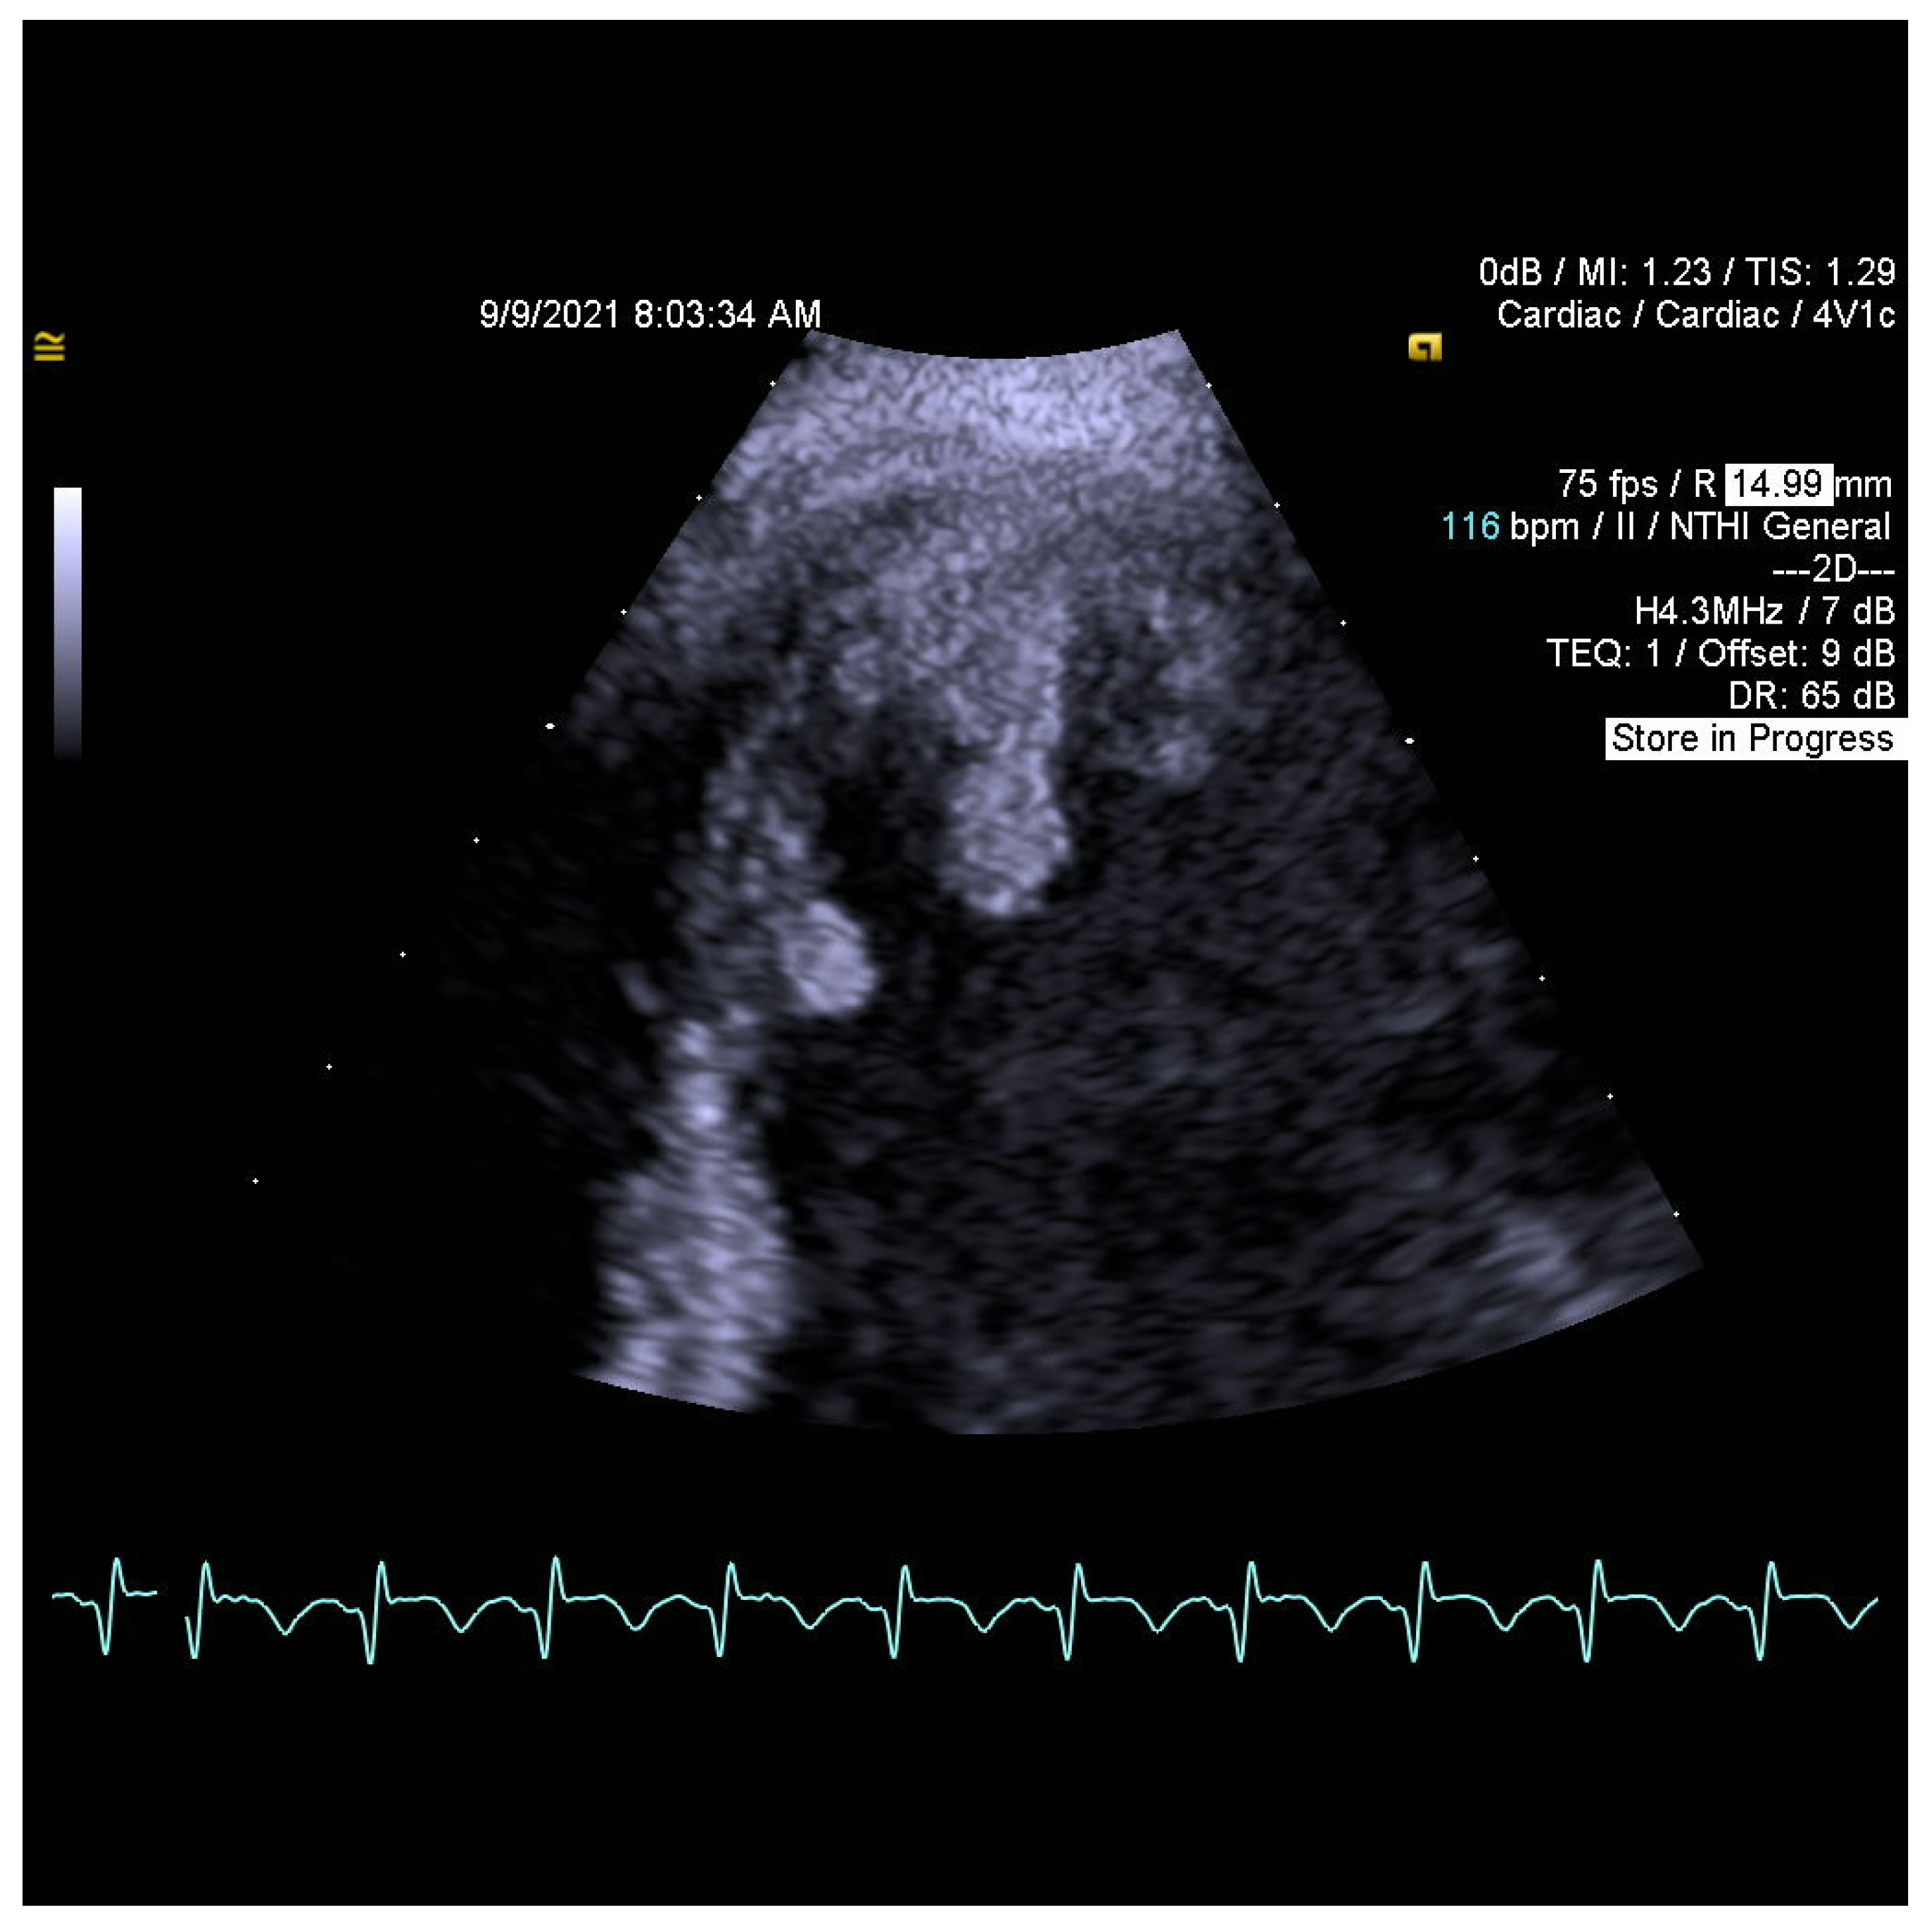

2. Case Report